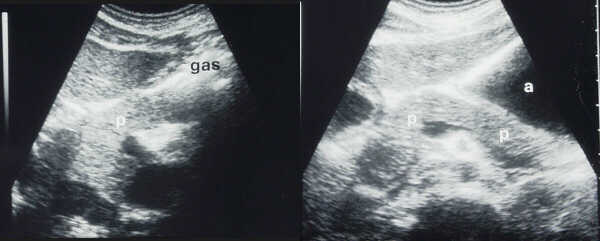

Transverse

supine scans. On the left, the head and the body of the pancreas (p) are well

visualized while the tail is obscured by gas in the stomach (gas). On the right

the stomach is fluid-filled (a) after drinking water. The pancreatic tail (p)

is well seen through the distended stomach.